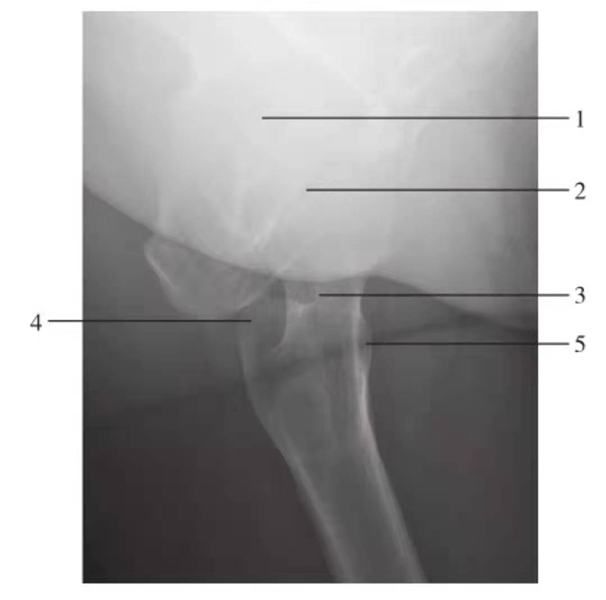

髋关节和股骨颈侧位

图3 髋关节和股骨颈侧位

1.髋臼;2.股骨头;3.股骨颈;4.大转子;5.小转子

髋关节蛙位片

图4 髋关节蛙位片

1.髂前上棘;2.骶髂关节;3.髂骨翼;4.髂前下棘;5.髂骨体;6.髋臼;7.关节间隙;8.股骨头;9.耻骨上支;10.坐骨支;11.耻骨联合;12.耻骨下支